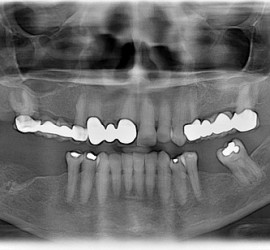

Ограничение или полная невозможность открывания рта. Этиология: рефлекторное тоническое сокращение жевательной группы мышц при различных патологических состояниях (столбняк, воспалительные процессы в челюстно-лицевой области и др.), анкилоз височно-нижнечелюстного сустава; рубцовые изменения околочелюстных тканей, слизистой оболочки, мышц, кожи с подкожной жировой клетчаткой. Клинические проявления характерные, ведущим симптомом является ограничение открывания рта различной […]